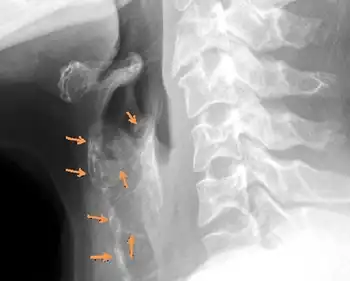

Being an extremely rare autosomal genetic disorder, differential diagnosis has only led to several cases since 1972. Initial diagnosis lends itself to facial abnormalities including sloping forehead, maxillary hypoplasia, nasal bridge depression, wide mouth, dental malocclusion, and receding chin.[5] Electroencephalography (EEG), computed tomography (CT) scanning, and skeletal survey are further required for confident diagnosis. Commonly, diffuse cartilage calcification and brachytelephalangism are identified by X-radiation (X-ray), while peripheral pulmonary arterial stenosis, hearing loss, dysmorphic facies, and mental retardation are confirmed with confidence by the aforementioned diagnostic techniques.[8]

Diagnosis is often confirmed by several abnormalities of skeletal origin. There is a sequential order of findings, according to Cormode et al., which initiate in abnormal cartilage calcification and later brachytelephalangism.[9] The uniqueness of brachytelephalangy in KS results in distinctively broadened and shortened first through fourth distal phalanges, while the fifth distal phalanx bone remains unaffected.[10] Radiography also reveals several skeletal anomalies including facial hypoplasia resulting in underdevelopment of the nasal bridge with noticeably diminished alae nasi. In addition to distinguishable facial features, patients generally demonstrate shorter than average stature and general mild developmental delay.

Cartilaginous effects

Many common effects sharing similarity with chondrodysplasia punctata stem from cartilaginous origin. Radiography reveals extensive diffuse cartilaginous calcification. Pulmonary angiography and soft tissue radiography often demonstrate significant cartilaginous ossification in the trachea and larynx, with perichondral and endochondral centers significantly ossified in transformed cartilage.[11] Abnormal diffuse cartilaginous ossification is typically most pronounced in the auricles and cartilage of the trachea and larynx, while peripheral pulmonary stenosis is frequently common in KS. In consanguineous parents of children with KS, one is often phenotypically normal, while the other is positive for pulmonary stenosis. Perhaps emanating from diffuse laryngotracheal calcification, patients often present with recurrent respiratory infection, otitis media, and sinusitis.[12]